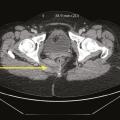

Névralgies pudendales

Le diagnostic de névralgie pudendale (NP) est clinique et comprend deux conditions incontournables  : la douleur est spontanée, de forme neuropathique à type de brûlures, coups d’aiguille, fer rouge, décharges électriques. Elle répond au score du questionnaire DN4.1 C’est le plus souvent une douleur violente sur l’échelle…